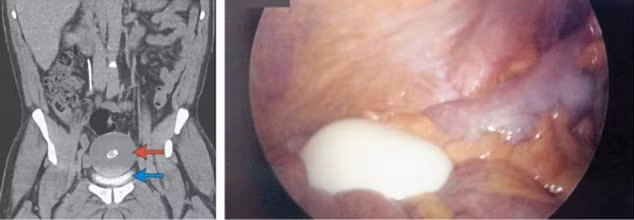

Phát hiện “quả trứng luộc” trong bàng quang một người đàn ông ảnh 1Hình ảnh của vật thể lạ trong bàng quang

Sau khi làm thủ tục khám và lấy các mẫu xét nghiệm gửi đến phòng thí nghiệm, các bác sĩ đã không tìm thấy gì khác thường trong cơ thể của người đàn ông. Tuy nhiên, họ đã sử dụng máy quét CT trong ổ bụng và phát hiện một vật thể lạ khổng lồ. “Nó tròn, vỏ mịn màng săn chắc, như một quả trứng bằng cao su, đang trôi nổi tự do trong bàng quang”, một bác sĩ mô tả.

Khối chất hình quả trứng đã được lấy ra từ cơ thể bệnh nhân sau phẫu thuật và cắt lớp để phân tích

Kết thúc cuộc phẫu thuật, các bác sĩ đã lấy ra được vật thể. Nó giống như một quả trứng luộc: dài đến 10cm, rộng 7,5 cm và nặng 220 g. Các bác sĩ cho biết đây là một dạng viêm bờm mỡ đại tràng (Epiploic  Appendages), túi mỡ bọc trong màng đại tràng tách ra, trôi nổi trong cơ thể và sẽ biến đổi thành một cục xơ khi bị vôi hóa.